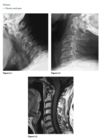

An axial gradient-recalled echo im-

age of the left shoulder shows a well-corticated

triangular bony structure in the region of the ac-

romion (Fig. 2.18.1, arrows). Proton-density and

T2-weighted, coronal, oblique MR images of the

shoulder show hypertrophic changes that involve

the acromioclavicular joint, causing impingement

and increased signal intensity within the distal

aspect of the supraspinatus tendon, indicative of

­ tendinosis

Os Acromiale

An os acromiale is a persistent sepa-

rate ossification center for the acromion that is as-

sociated with rotator cuff tendon impingement and

tearing.

The os acromiale (Fig. 2.18.3, axillary radiograph,

arrow), with its smooth sclerotic margins, can be

easily distinguished from an acute acromial fracture

(Fig. 2.18.4, anteroposterior radiograph, arrows)

since an acute fracture has no sclerosis around the

fragment.